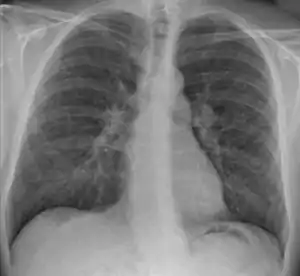

![]() Рентгенограма легень з гранульомами при саркоїдозі Рентгенограма легень з гранульомами при саркоїдозі | |

Збільшення лімфатичних вузлів середостіння часто виявляють випадково при рентгенологічному дослідженні, але воно може поєднуватися з ураженням легень, яке проявляється задишкою, кашлем, наявністю вологих хрипів. При рентгенологічному дослідженні у легенях виявляють множинні дрібні тіні, що нагадують туберкульоз. Пізніше розвивається пневмофіброз з явищами дихальної недостатності. Спостерігають різні ураження шкіри, зокрема вузлувату еритему. Серцева патологія проявляється найчастіше порушеннями провідності аж до повної поперечної блокади. Відмічають також патологічні зміни в очах, нервовій системі, скелетних м'язах.